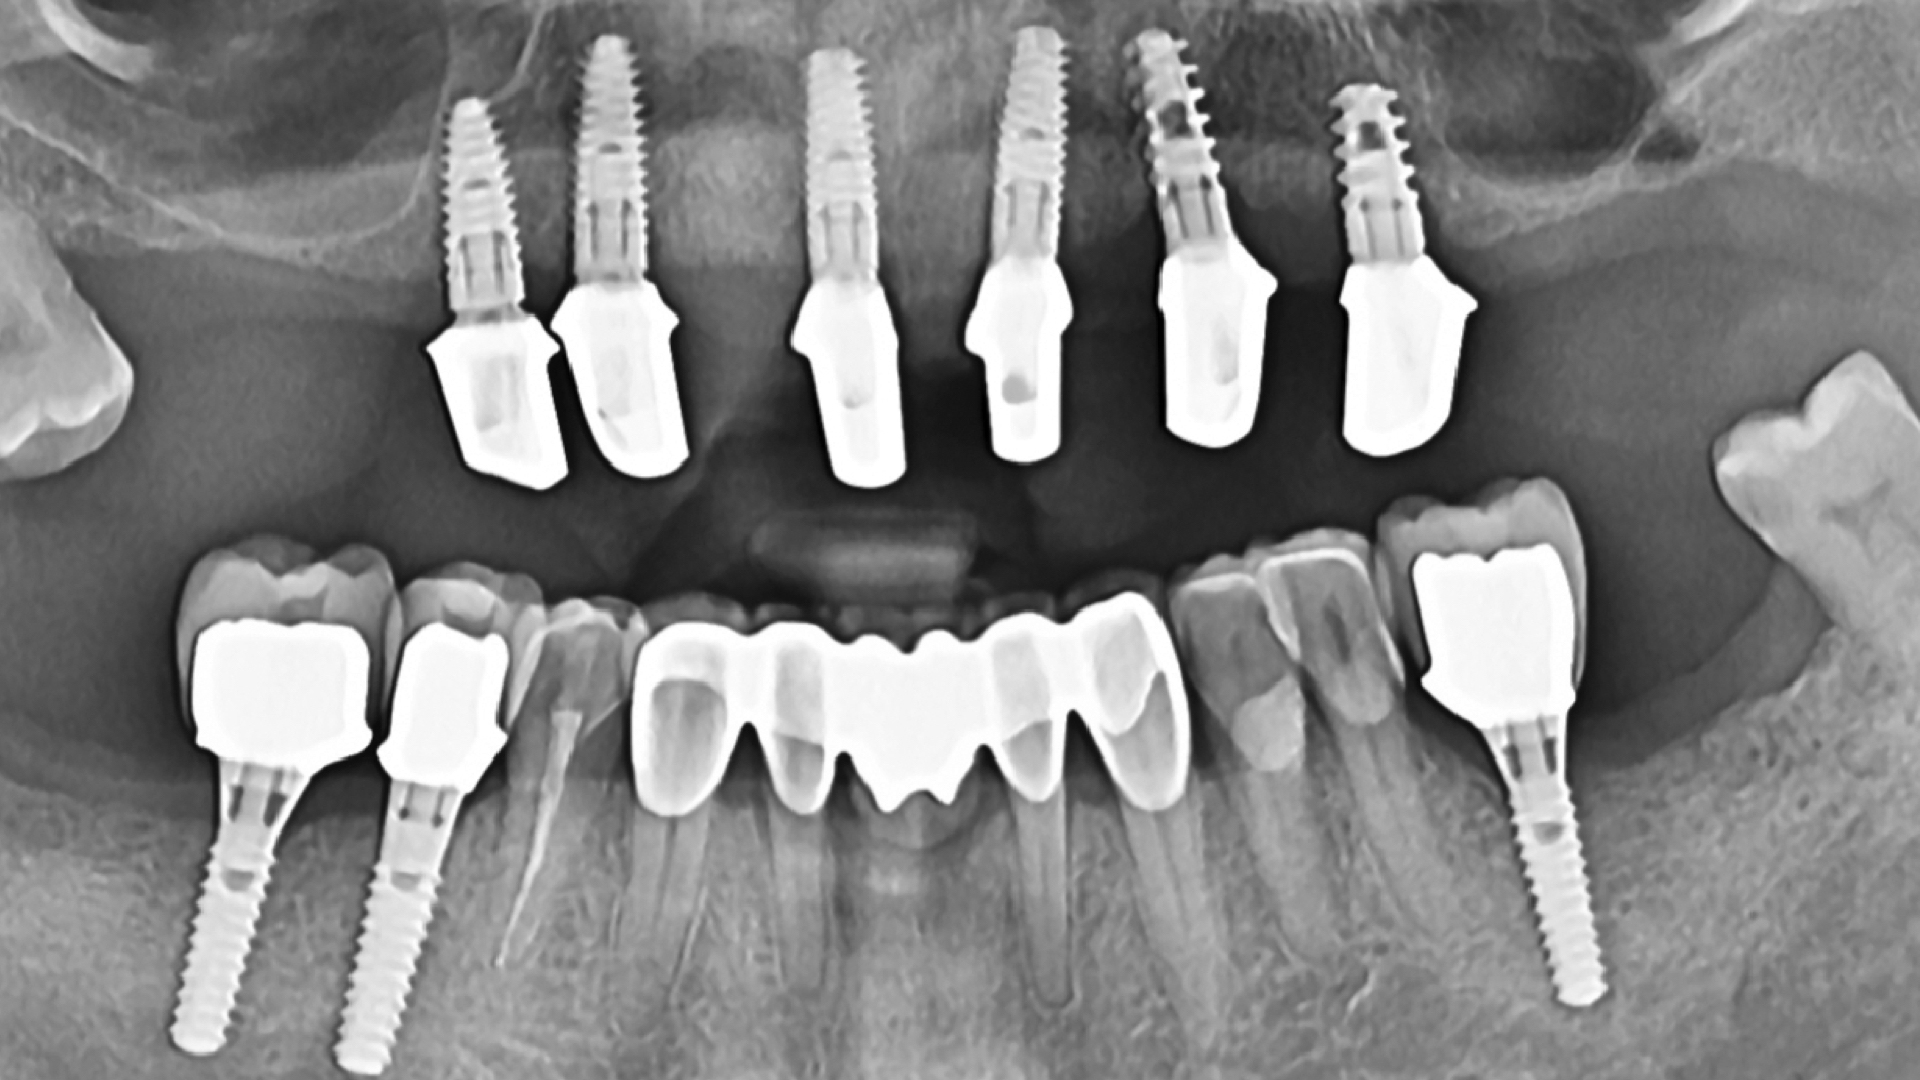

După cum se poate vedea în fotografii, pe maxilar, domnul rămăsese fără dinți, iar pe mandibulă mai avea câțiva rămași. Am reușit să salvăm majoritatea dinților de pe mandibulă, realizând tratamente endodontice și restaurându-i cu fațete și coroane dentare, iar acolo unde au fost lipsă s-au inserat implanturi, peste care s-au pus mai apoi coroane integral ceramice. Pentru maxilar s-a agreat soluția de proteză dentara totala pe telescoape galvano-formate pe implanturi, cu gingie individualizată, pentru un rezultat cât mai estetic și durabil.

Proteza dentara telescopata este o proteza totala fixa, dar si mobila. Permite pacientului sa o inlature pentru o igienizare completa si corecta.